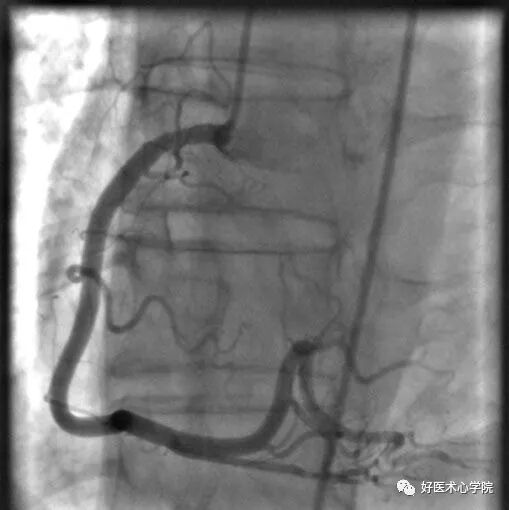

左前斜位:观察右冠全长,但难以看到远段分叉。

此时可以加足位可以观察。

造影导丝是什么珍藏 冠脉造影从流程到诊断,基础必备!_https://www.jmylbn.com_新闻资讯_第53张

△左前斜位下的右冠